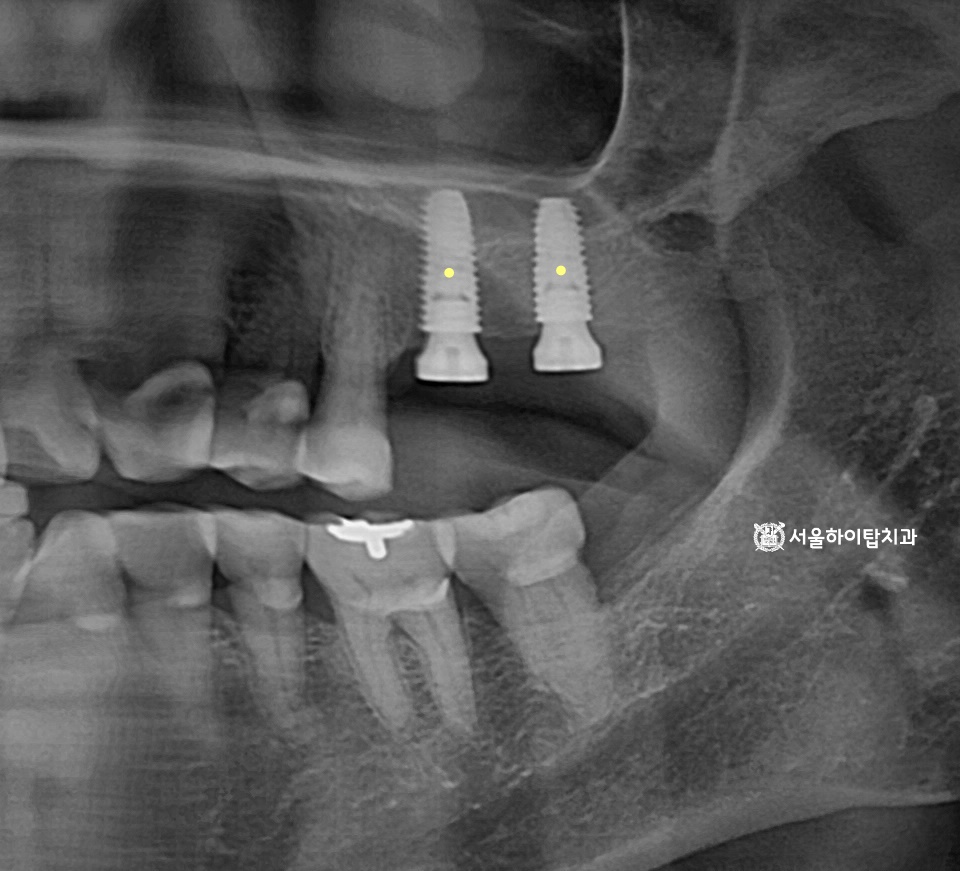

십정동 치과 상실된 치아가 불러오는 연쇄적 문제? 치조골 흡수와 기울어진 어금니, 뼈이식 동반 임플란트 과정 동암역 치과 : 균형 잡힌 저작이 중요한 이유, 전반적으로 손상된 치아 및 잇몸 임플란트를 통해 저작 기능 개선 간석역 치과 치주염으로 인한 치조골 흡수, 치아 파절 및 마모까지 임플란트 가상 시뮬레이션을 통한 안전한 수술 과정 1 2 Next Archives 2026년 4월 2026년 3월 2026년 2월 2026년 1월 2025년 12월 2025년 11월 Categories 미분류 신경치료 심미 치료 임플란트